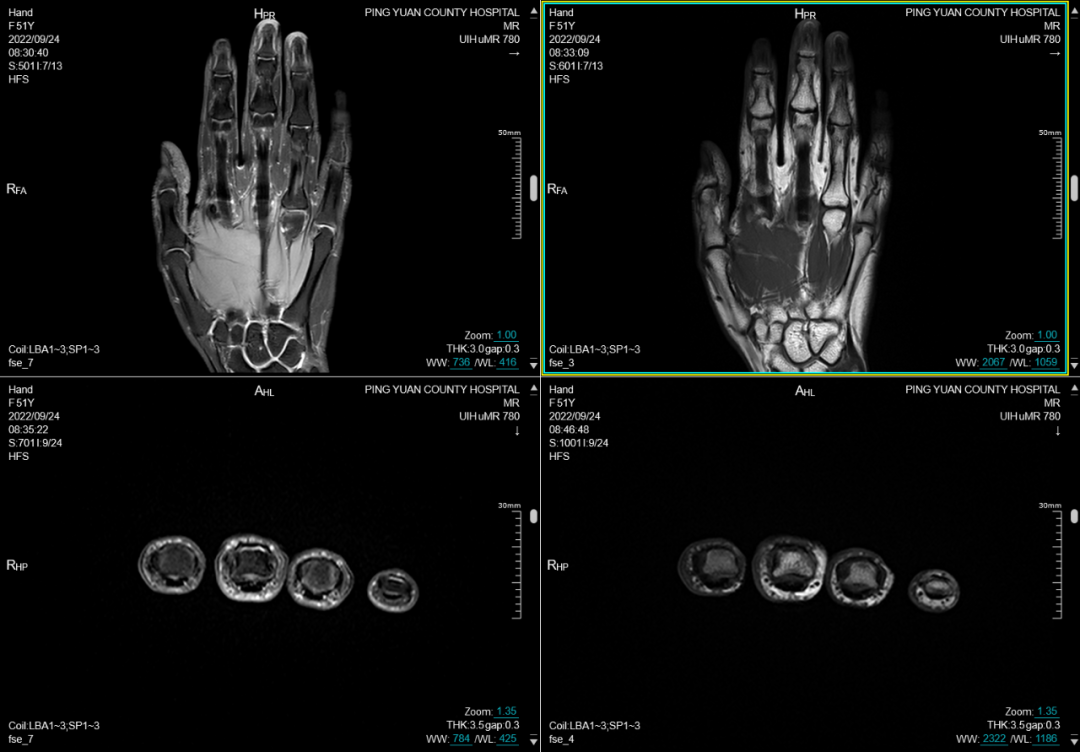

六、在四肢及关节检查方面:图像更清晰,后处理功能更丰富

MRI彻底变革了骨骼肌肉结构的成像,主要应用于创伤、关节炎、肿瘤和感染等方面。在创伤方面可显示平片或CT不能显示的病变如骨挫伤或骨小梁骨折,隐匿性骨折平片甚至CT易漏诊,而MRI能清晰显示。MRI是无创评估关节内软骨的最佳检查手段,能清晰观察软骨细微变化。

(手掌平扫)